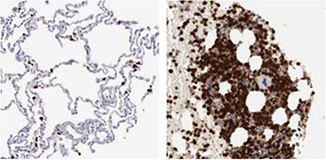

There are two Anti-RBM3 antibodies in Atlas Antibodies' product catalog; the polyclonal HPA003624 and the PrecisA Monoclonal AMAb90655. The monoclonal Anti-RBM3 antibody AMAb90655 has shown excellent specificity in Western blot analysis of human cell lines, and is routinely used for staining of formalin fixed paraffin embedded tissue in IHC (Figure 3).

Figure 3. Immunohistochemical analysis of RBM3 expression in breast cancer (left) and prostate cancer (right) using AMAb90655 shows nuclear positivity in tumor cells. The WB image shows an expected band of 17 kDa in human cell line RT4 lysate using AMAb90655.